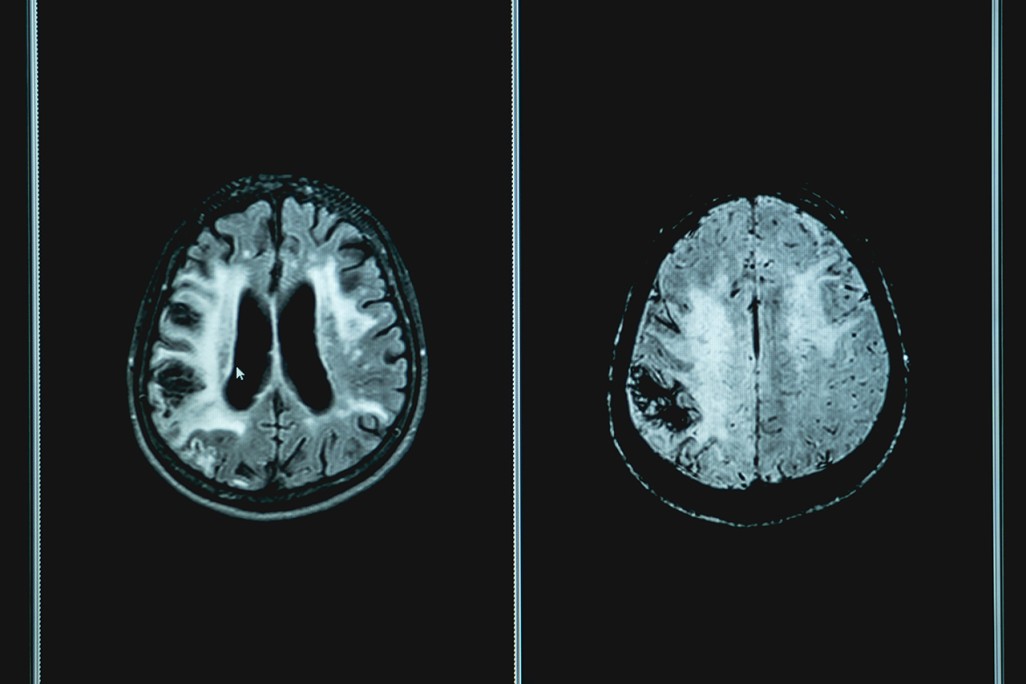

심뇌혈관질환 소뇌위축증

소뇌에 퇴행적 변화가 발생해 크기가 작아져 운동능력을 잃어버리는 질환

소뇌는 몸의 균형을 유지하기 위한 중심 기관으로 자세를 안정적으로 유지해 주며 척추를 통해 들 어온 감각정보 및 뇌 영역신호들을 종합해 정밀하게 운동기능을 수행할 수 있도록 도와준다. 술에 취한 듯한 걸음걸이가 파킨슨병과 차별되는 특징이며 몸이 한쪽으로 쏠림, 물건을 집으려 할 때 손 떨림, 물체가 흔들려 보임, 발음이 꼬임 등이 있을 수 있다.